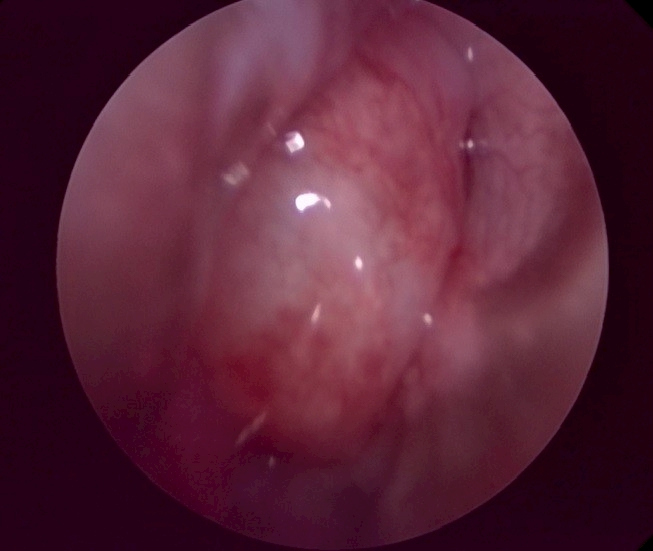

鼻腔內視鏡可見異常: 發炎、團塊、鼻甲糜爛、真菌斑塊、寄生蟲、異物。

圖示為鼻腔深部清洗出的膿液、鼻腔團塊、鼻黏膜糜爛。